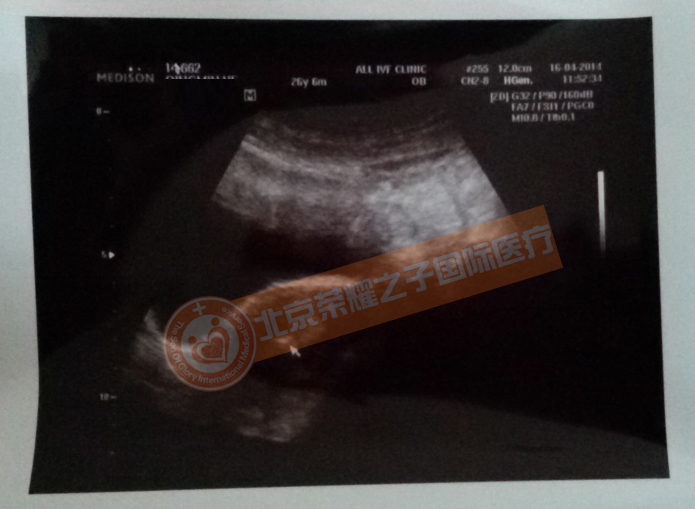

10月31日,我回国后又一次去到医院进行彩超验孕,可以看到我肚子里的胎儿正在健康成长。